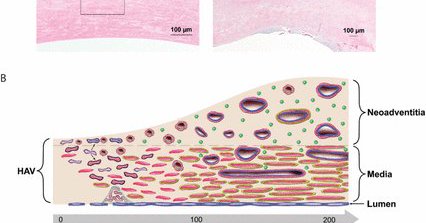

@farkomd @AlanLumsdenMD @AWBeckMD @westleyohman @MaherSabalbal @AmputationSuck Trauma paper you might enjoy from @TSACO_AAST “Short-term performance of Symvess (acellular tissue engineered vessel-tyod) compared to external control data for autologous vein in treatment of extremity arterial injury” https://t.co/quOVh7IQPF

tsaco.bmj.com

Background To evaluate the short-term clinical performance of Symvess (acellular tissue engineered vessel-tyod), formerly known as human acellular vessel, or HAV, compared with autologous vein for...